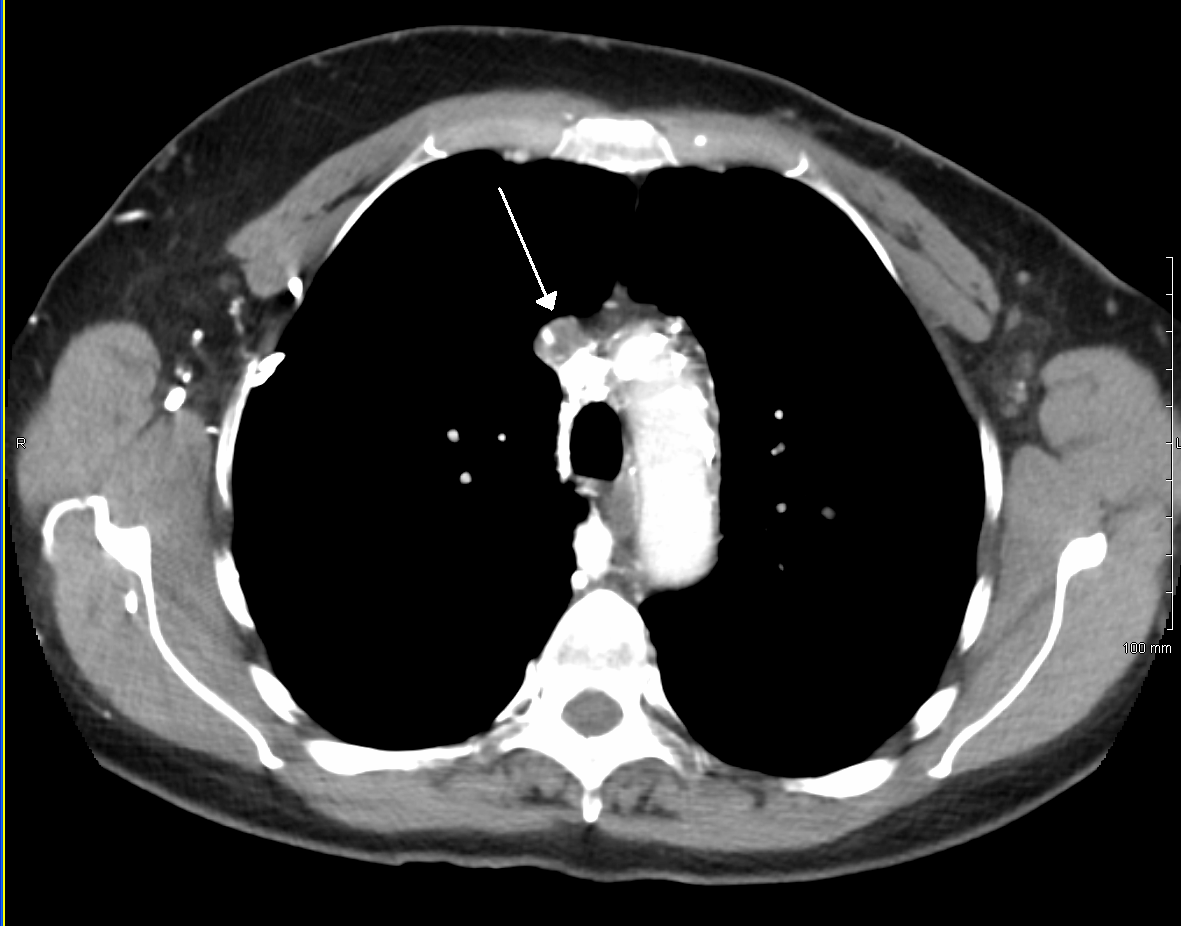

상대정맥 증후군(SVCS)을 진단하는 주요 기술에는 흉부 X-레이, CT 스캔, 기관지 내시경 검사 시 경기관지 바늘 흡인 및 종격동경 검사가 있다.[7] 흉부 X-레이는 종격동 확장을 보여줄 수 있으며, 상대정맥 증후군의 주된 원인을 나타낼 수 있다.[7] 그러나 상대정맥 증후군 환자의 16%는 정상적인 흉부 X-레이 소견을 보인다. CT 스캔은 조영 증강을 해야 하며, 목, 가슴, 하복부 및 골반에 대해 촬영해야 한다.[7] CT 스캔은 또한 근본적인 원인과 질병의 진행 정도를 보여줄 수 있다.[7]